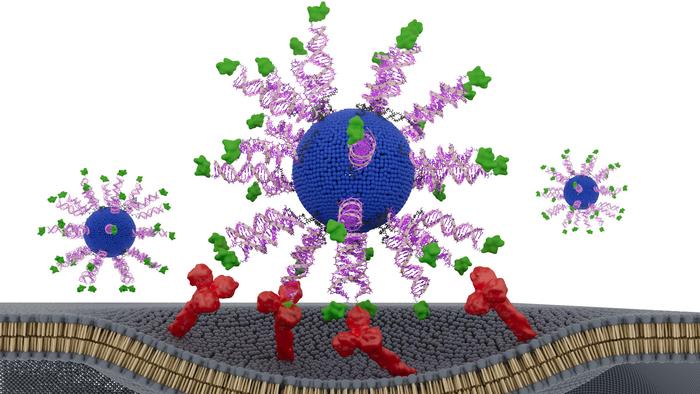

To address this, the researchers designed three SNA‑based vaccines containing identical components: a lipid core, CpG adjuvant, and a short HPV16 E711‑19 peptide. The only difference was how the antigen was displayed. One formulation buried the peptide inside the nanoparticle, while two others attached it to the surface through either the N‑terminus or C‑terminus—a small structural shift with potentially large immunological consequences.

The differences were striking. All three SNAs enhanced dendritic cell activation and CD8⁺ T‑cell cytotoxicity compared to a simple peptide‑adjuvant mixture, but the N‑terminally displayed version, dubbed N‑HSNA, consistently outperformed the others. It induced roughly eight‑fold higher interferon‑γ secretion and about 2.5‑fold greater cytotoxicity in primary human cells, the authors wrote.

The findings highlight the emerging field of “structural nanomedicine,” which emphasizes the deliberate arrangement of vaccine components rather than simply mixing them together—what lead author Chad A. Mirkin, PhD, calls the “blender approach.”